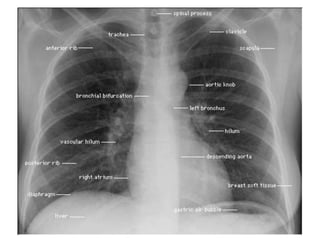

Normal Chest X-Ray

Scheme of viewing PA film

1. Request form                Name ,age, sex, date, clinical information

2. Technical                   View

Centering, patient position

Side Markers

Adequate inspiration

Exposure/Penetrance

3. Soft tissue and bony cage   Subcutaneous emphysema, fractures

4.Trachea                      Position, Outline

5. Heart and Mediastinum       Shape , Size, Displacement

6.Diaphragms                   Outline ,Shape , Relative position

7.Pleural spaces               Position of horizontal fissure,

costophrenic and cardiophrenic angles

8.Lungs                        Local , generalized abnormalities,

comparison of translucency and vascular

marking sof the lungs

9.Hidden areas            Apices, Posterior sulcus, Mediastinum,

Hila, Bones

10. Hila                  Density, Position, Shape

11. Below the Diaphragm   Gas shadows, Calcification